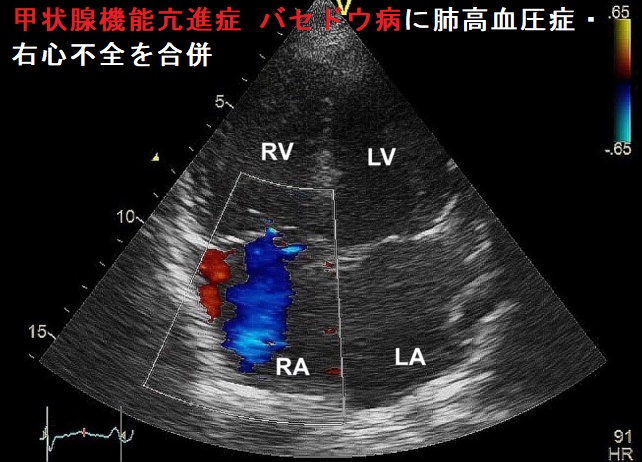

- 心エコー検査;推定肺動脈収縮期圧上昇

甲状腺機能亢進症 バセドウ病に肺高血圧症・右心不全を合併し、三尖弁閉鎖不全症(TR)も伴う。[Endocrinol Diabetes Metab Case Rep. 2018 May 16:2018:18-0012.]